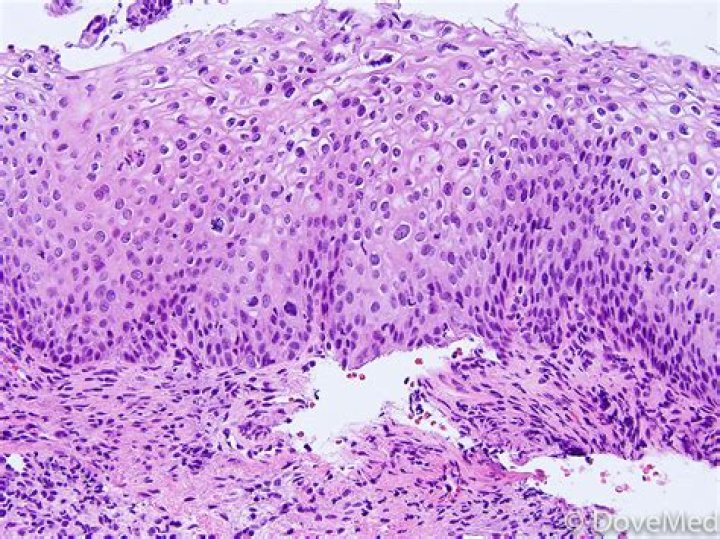

How is condyloma diagnosed

Condylomas are most often detected with the naked eye. … In case of doubt, the doctor can do a biopsy.For people who have no symptoms, no test is available to detect the virus.No test is currently available to screen specifically for HPV.

What does condyloma acuminata look like?

Genital warts appear as flesh-colored, round bumps of varying sizes. They can be smooth and flat or cauliflower-like with a small stalk. They can be seen on the labia, vagina, penis, scrotum, anus, skin around the anus, and urethra.

Is condyloma acuminata precancerous?

Condylomata acuminata are caused by HPV isotypes that do not cause cancer. Accordingly, these genital warts are not precancerous and do not progress to invasive carcinomas.

Condylomata acuminata, or genital warts, are proliferative lesions of genital epithelium caused by human papillomavirus (HPV) infection. HPV types 6 and 11 are most often detected in these lesions.